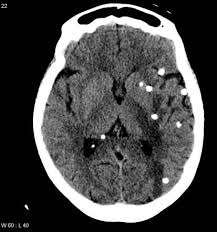

Unenhanced And Enhanced Axial Cts Of Brain Shows A Large Serpiginous Avm Adjacent To The Tentorium Radiology Imaging Radiology Interventional Radiology